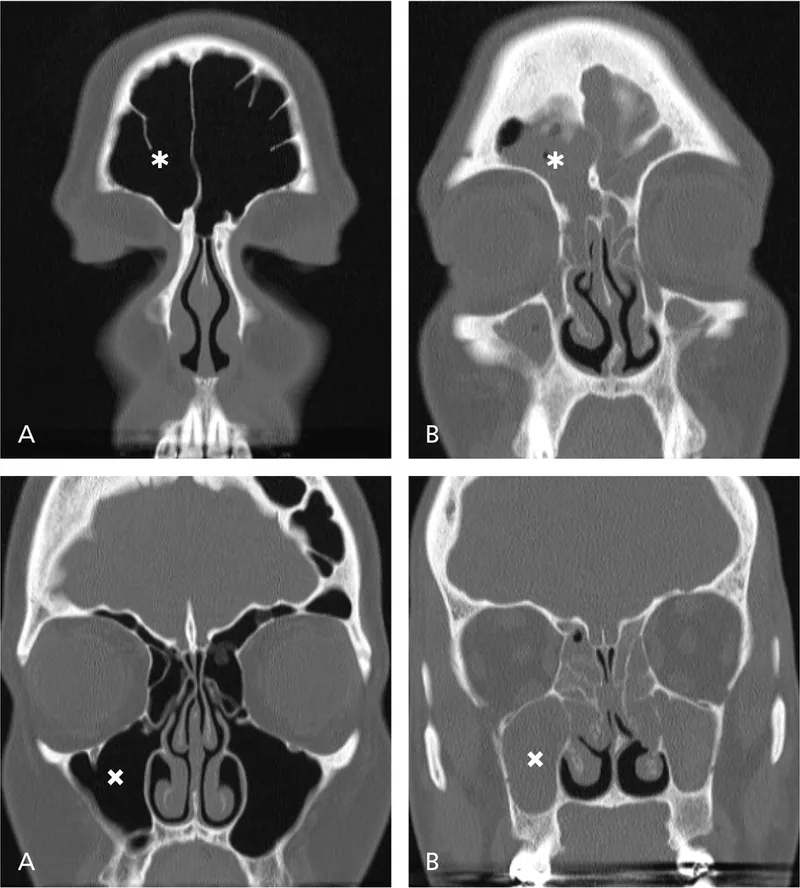

Sinusitis - A Nasty Nasal Network

Chronic Rhinosinusitis (CRS) & Biofilms

- Biofilms are a primary driver in CRS, especially with nasal polyps (CRSwNP).

- They create a persistent nidus of infection, leading to recalcitrant disease.

Pathophysiology

- The biofilm's extracellular matrix shields bacteria from antibiotics and host immune responses.

- This triggers chronic inflammation, leading to mucosal edema and impaired mucociliary clearance.

⭐ Biofilms are detected in over 80% of mucosal specimens from patients undergoing surgery for CRS.